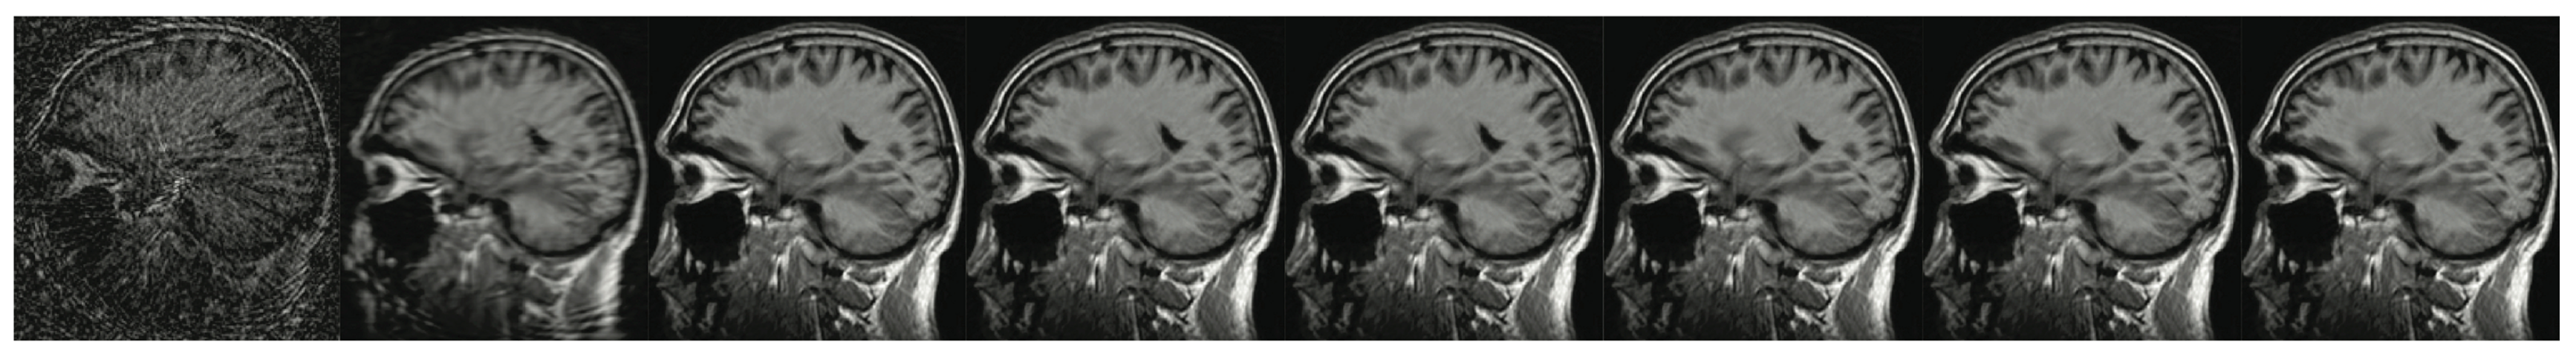

Figure 7. The brain imaging results. From left to right: A: Image reconstructed from partially sampled PROPELLER blade, B:Cartesian sampling grid without image registration applied (with no downsampling applied), C: B-spline Cubic interpolation, D: Non-Rigid Multi-Modal 3D Medical Image Registration Based on Foveated Modality Independent Neighbourhood Descriptor [45], E: Enhanced deep residual networks for single image super-resolution [14], F: Image super-resolution using very deep residual channel attention networks [16], G: Residual dense network for image super-resolution [15], H: super-resolution with proposed sampling scheme and motion compensation (the proposed algorithm). Compression ratio is 50%. Please see Table 2 for the PSNR values at other compression ratios.